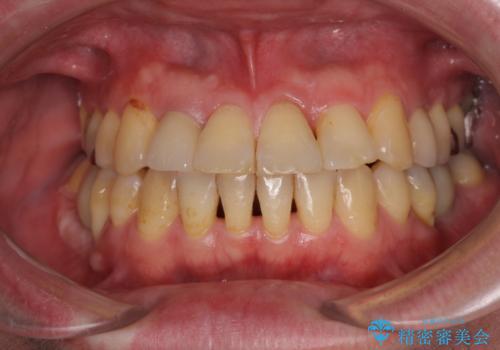

矯正治療でインプラント埋入を行い、矯正治療後に気になる前歯と合わせてオールセラミッククラウンによる補綴治療を行うこととしました。

骨造成や歯肉移植など、治癒期間の長い処置を必要としたため治療期間は長くなりましたが、安定した咬み合わせと整った歯列となり、患者様には大変満足していただきました。